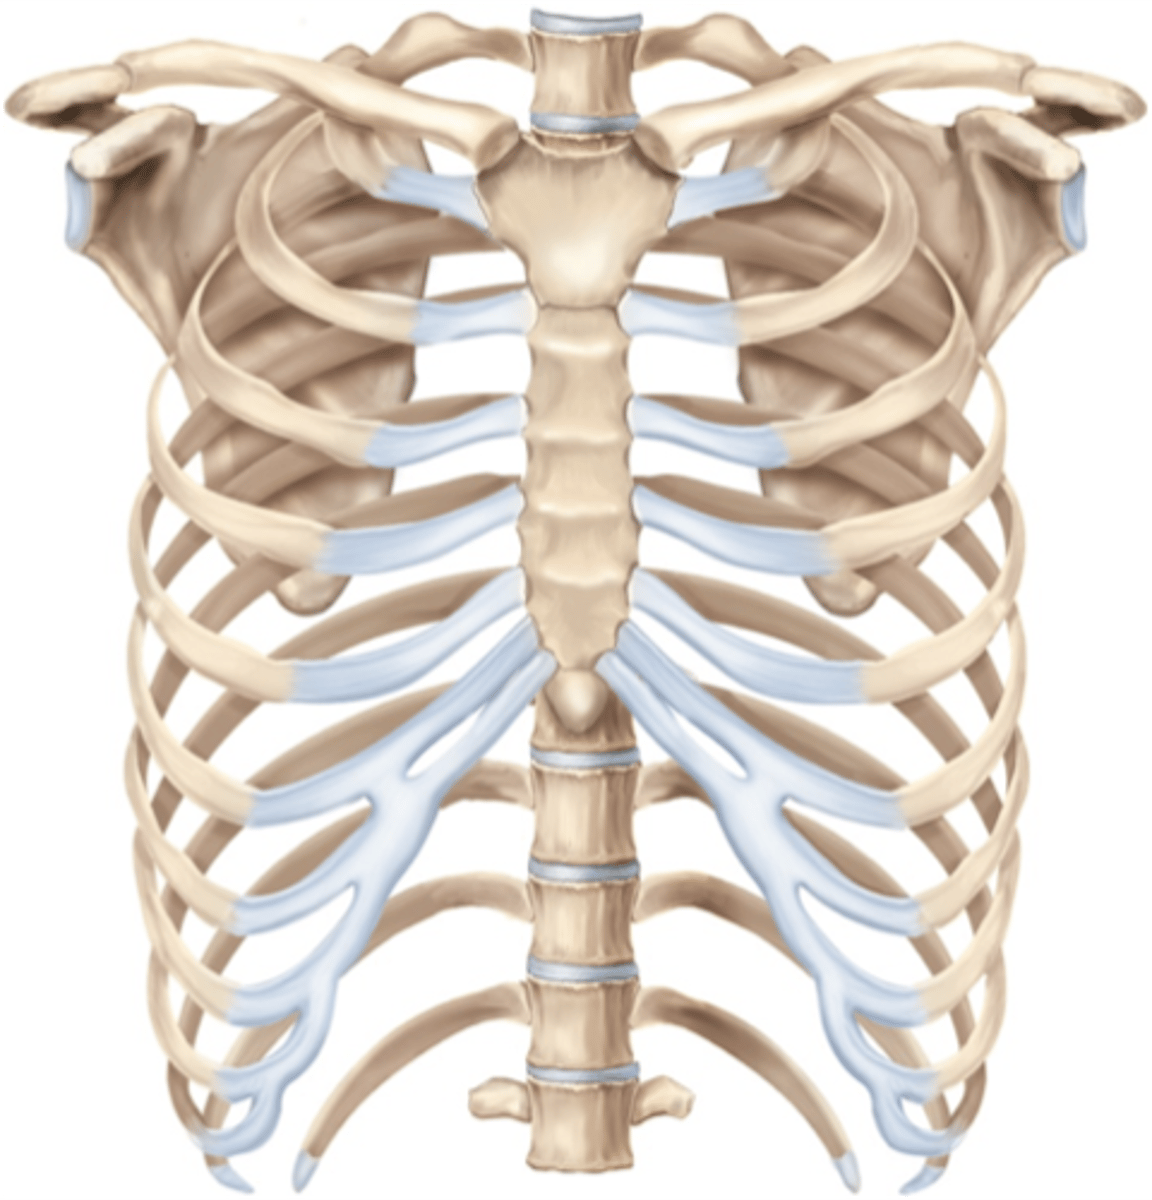

What makes up the thoracic cage?

sternum, ribs, and thoracic vertebrae

Which are the true ribs and what makes them "true" ?

1-7, attach directly to sternum via costal cartilage

Which are false ribs? Why?

ribs 8, 9, 10 (usually), attach directly to sternum but by the cartilage of the superior rib

Which are the "floating ribs" and why?

11-12, Don't attach in any way to sternum

How is the costal cartilage numbered?

by the rib it articulates with

What does the sternum articulate with at its joints?

clavicles, ribs 1-7

1st sternocostal joint

synarthrosis and synchondrosis - starts off cartilaginous and fuses in adulthood

2nd-7th sternocostal joints

Synovial, diarthrodial, plane (gliding)